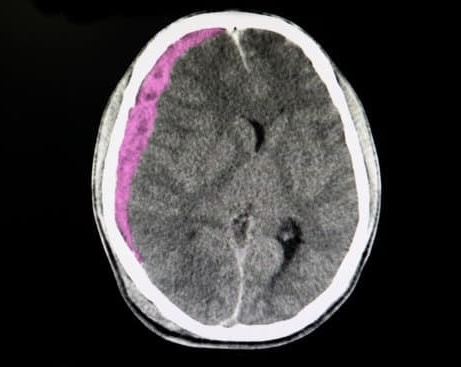

두개골 절개술(Craniotomy)는 두개골(머리뼈)의 일부를 절개하여 뇌에 직접 접근하는 외과적 수술입니다.

이 절차는 뇌종양 제거, 뇌출혈 치료, 동맥류 수술, 외상성 뇌손상 등의 다양한 뇌 관련 질환을 치료하기 위해 시행됩니다.

혈종 제거: 뇌출혈로 인해 뇌 안에 고인 피(혈종)를 제거하고 뇌의 압력을 감소시키기 위해 필요합니다.

뇌 접근: 두개골이 제거된 후 뇌에 접근하여 문제를 해결합니다. 뇌종양을 제거하거나 출혈 부위를 복구하는 등의 절차가 시행됩니다.